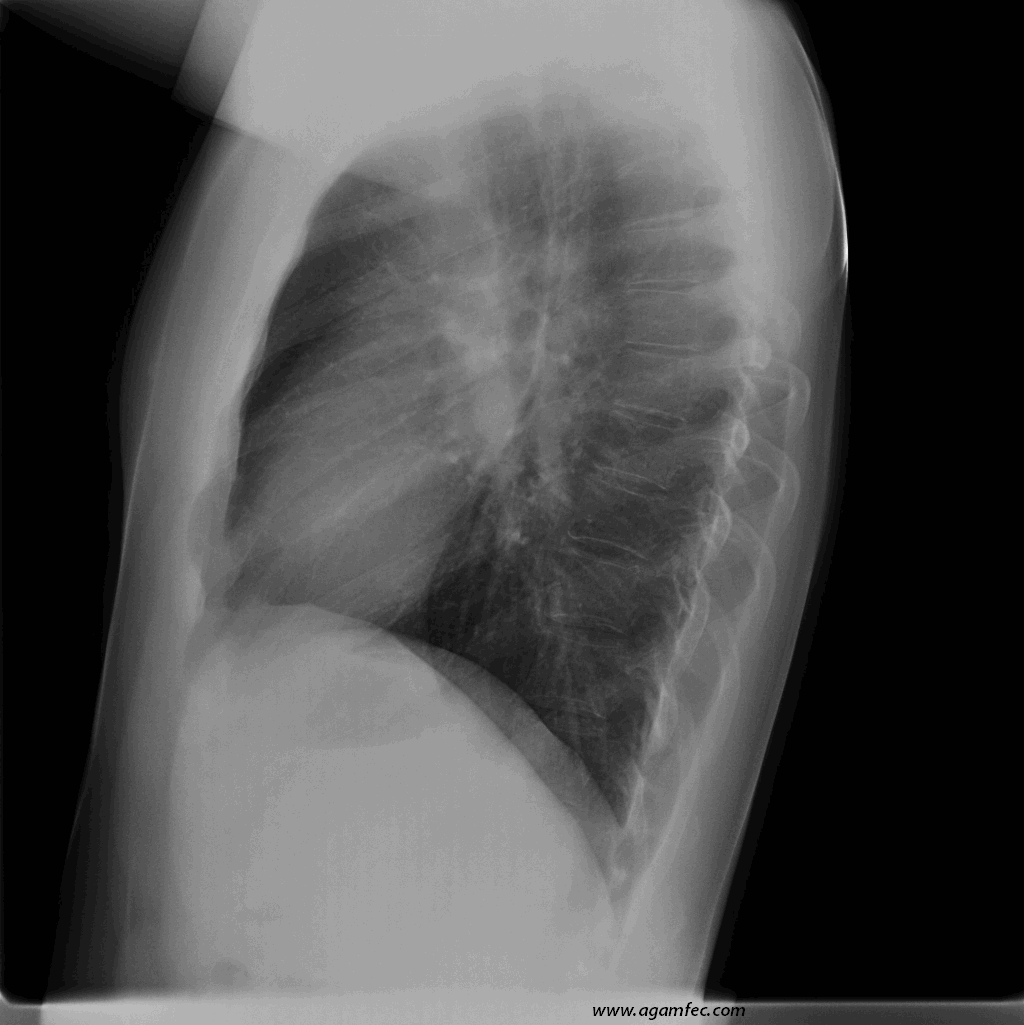

Figura 1. Radiografía de tórax PA y lateral de paciente con Eritema Nodoso, en la que se observan adenopatías hiliares bilaterales, sugestivas de Sarcoidosis